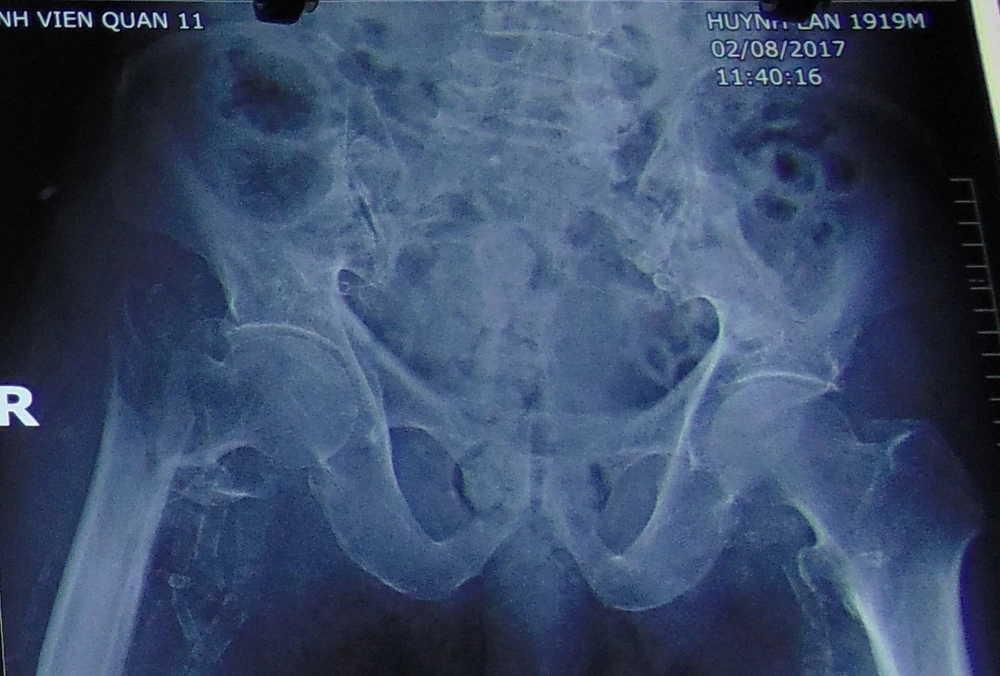

Kết quả chụp X quang cho thấy ông L bị gãy khớp háng chân phải. Ảnh: TRẦN NGỌC

Kết quả chụp X-quang cho thấy ông L. bị gãy khớp háng chân phải. Ảnh: TRẦN NGỌC